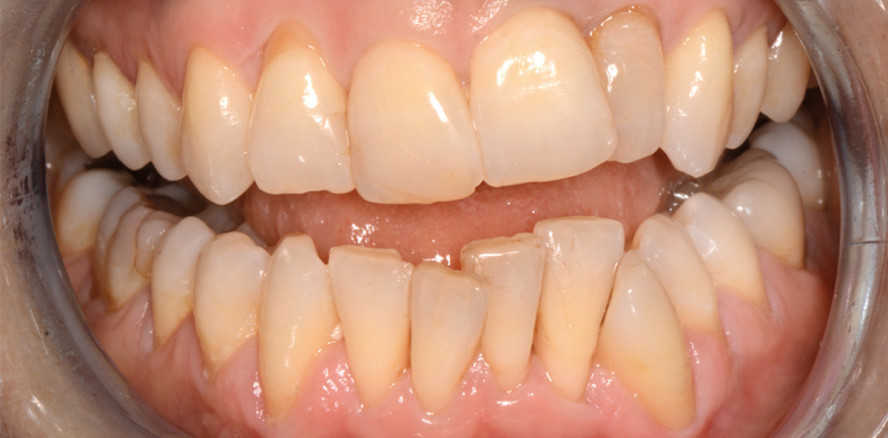

Abb. 1b–c: Frontale Ansicht der Okklusion bei geschlossenem und offenem Mund. Man sieht die ungleiche Inklination und Angulation der Kronen, den ausgeprägten anterioren Engstand im Unterkiefer, die bukkale Rezession (hauptsächlich um Zahn 33) und den Abrieb der Inzisalkanten der oberen und unteren Frontzähne. © Rafi Romano DMD, M.Sc.

Die 47-jährige Patientin stellte sich wegen des von ihr als unästhetisch wahrgenommenen Erscheinungsbildes ihrer Zähne in der Klinik vor. Es lagen ein stark ausgeprägter Engstand in der unteren Front, eine geneigte obere Okklusionsebene, eine asymmetrische Lachlinie, eine mesiale Kippung des unteren linken Eckzahns sowie eine nur noch minimale knöcherne Einbettung von Zahn 32 (linker unterer seitlicher Schneidezahn) mit einer tiefen Parodontaltasche von 7 mm vor (Abb. 1a bis 1g).